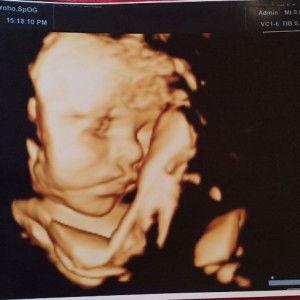

Bun sharing dong ada yg Hb nya rendah saat trimester 3? apa solusi nya selain minum vit tambah darah supaya Hb bagus. saya usia 31 week cek darah hasil Hb nya 9.7 , normal nya itu 12 sampai 14 Bun . skrg jadi was² Hb nya gak normal mendekati lahiran . kalau Hb rendah sangat dikhawatirkan pendarahan saat melahirkan. ?